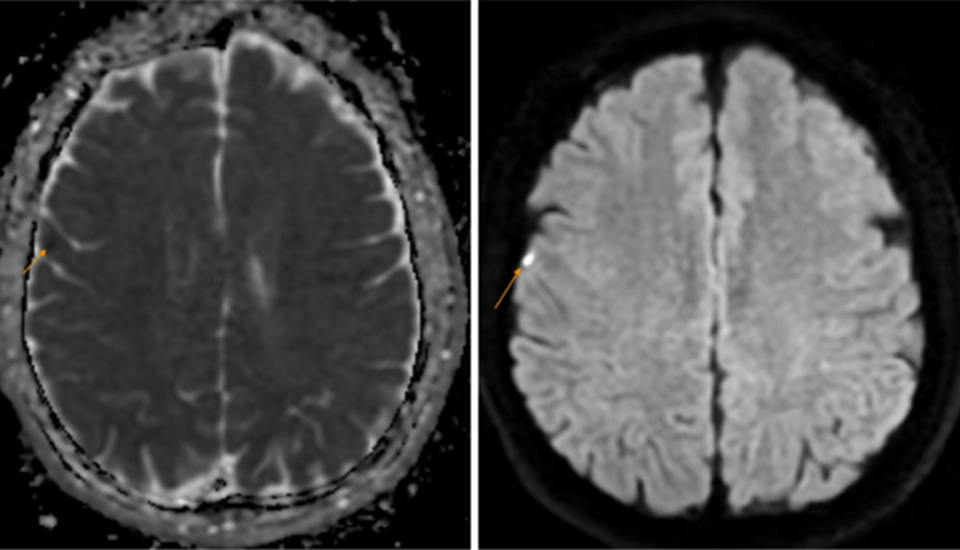

Sau khi thăm khám lâm sàng, bệnh nhân được chỉ định thực hiện một số xét nghiệm, chẩn đoán hình ảnh chuyên sâu nhằm tìm ra chính xác nguyên nhân của hiện tượng bất thường. Trên phim chụp MRI não phát hiện hình ảnh tổn thương nhỏ vỏ não vùng đỉnh phải (theo dõi nhồi máu não) kèm thoái hóa myelin chất trắng dưới vỏ bán cầu đại não và quanh não thất bên hai bên.

Hình ảnh tổn thương được phát hiện trên phim chụp MRI não